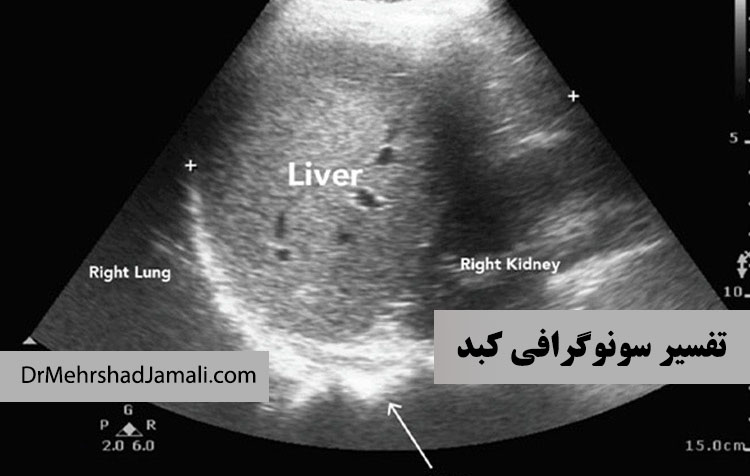

تفسیر نتایج سونوگرافی کبد

سونوگرافی کبد شما می تواند چیزهای زیادی در مورد آن نشان دهد. یک ارائه دهنده مراقبت های بهداشتی ممکن است سونوگر